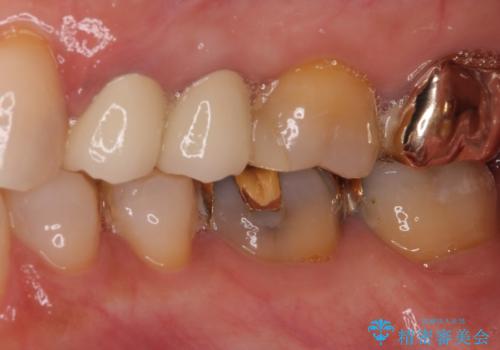

- 歯肉が退縮したためにクラウンの縁や歯根が見えてしまっていることを気にして来院された患者様です。

また、歯肉が黒く変色していることも気になるとのことでした。

仮歯に変える際に歯肉の一部を切除し、金属片による変色を除去した後、オールセラミッククラウンにて補綴することとしました。

メタルタトゥー(金属イオンの溶出による歯肉の変色)は、歯に装着された金属から金属イオンが溶け出したり、金属を除去するときの切削片が歯肉に入り込んでしまったりして引き起こされます。

物理的に除去をすることできれいな歯肉となりますが、残留している金属イオンにより再発するリスクがあります。